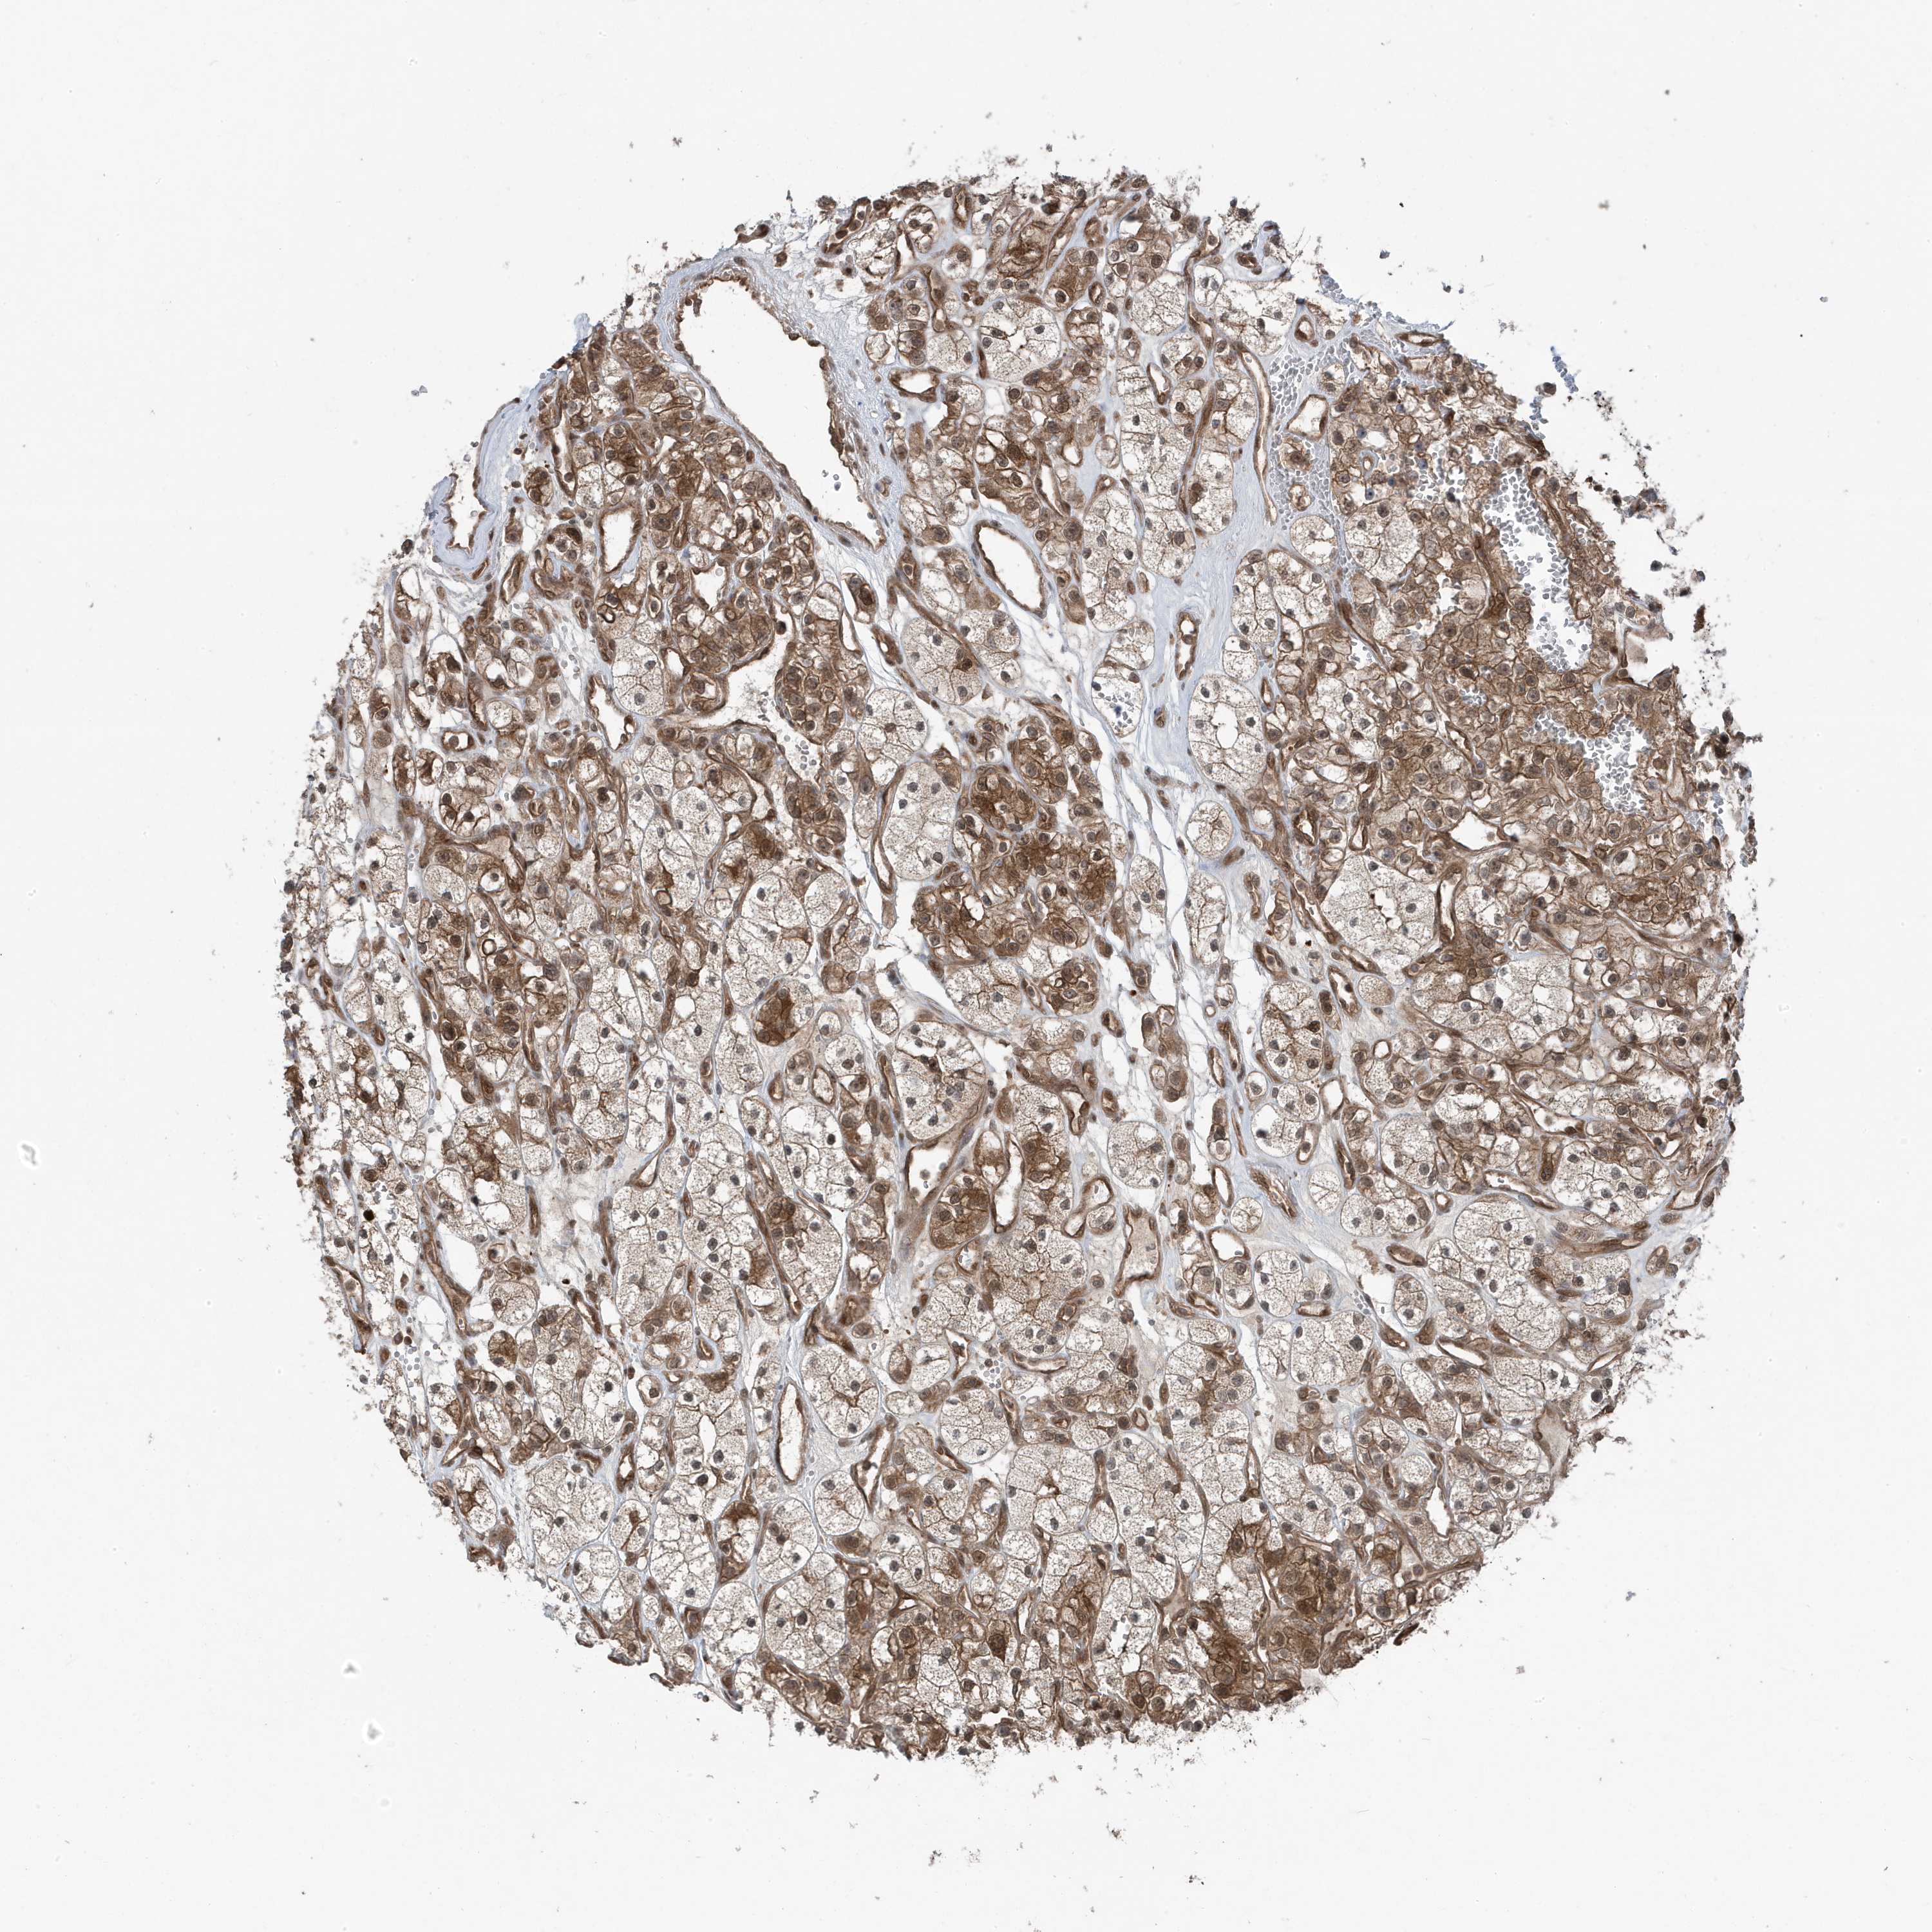

KIDNEY RENAL CLEAR CELL CARCINOMA (VALIDATION) - Interactive survival scatter ploti

The Survival Scatter plot shows the clinical status (i.e. dead or alive) for all individuals in the patient cohort, based on the same data that underlies the corresponding Kaplan-Meier plots. Patients that are alive at last time for follow-up are shown in blue and patients who have died during the study are shown in red.

The x-axis shows the expression levels (FPKM) of the investigated gene in the tumor tissue at the time of diagnosis. The y-axis shows the follow-up time after diagnosis (years). Both axes are complimented with kernel density curves demonstrating the data density over the axes. The top density plot shows the expression levels (FPKM) distribution among dead (red) and alive patients (blue). The right density plot shows the data density of the survived years of dead patients with high and low expression levels respectively, stratified using the cutoff indicated by the vertical dashed line through the Survival Scatter plot. This cutoff is automatically defined based on the FPKM cutoff that minimizes the p-score. The cutoff can be changed by dragging the vertical line or by entering a cutoff value in the square labeled "Current cut-off".

Under the Survival Scatter plot the p-score landscape (black curve; left axis) is shown together with dead median separation (red curve; right axis). Dead median separation is the difference in median mRNA expression between patients who have died with high and low expression, respectively. It is calculated as follows: median FPKM expression of dead patients with high expression - median FPKM expression of dead patients with low expression. This is intended to aid the user in visually exploring custom cutoffs and the associated p-scores and dead median separation.

Individual patient data is displayed and can be filtered by clicking on one or more of the category buttons on the top of the page. Categories describing expression level and patient information include: high, low, alive, dead, female, male and tumor stages. The scale of the x-axis can be toggled between linear and log-scale by clicking on the "x log" button. Mouse-over function shows TCGA ID, patient information and mRNA expression (FPKM) for each patient.

& Survival analysisi

Kaplan-Meier plots summarize results from analysis of correlation between mRNA expression level and patient survival. Patients were divided based on level of expression into one of the two groups "low" (under cut off) or "high" (over cut off). X-axis shows time for survival (years) and y-axis shows the probability of survival, where 1.0 corresponds to 100 percent.

MAPK1IP1L is not prognostic in Kidney Renal Clear Cell Carcinoma (validation)

Best expression cut offi

Based on the FPKM value of each gene, patients were classified into two groups and association between prognosis (survival) and gene expression (FPKM) was examined. The best expression cut-off refers the FPKM value that yields maximal difference with regard to survival between the two groups at the lowest log-rank P-value. Best expression cut-off was selected based on survival analysis .

When clicking on this number, the vertical dashed line indicating cut-off, the interactive survival plot, and the Kaplan-Meier curve will be adjusted to show results based on the best expression cut-off.

: 42.94

TCGA RNA samplesi

RNA-seq data is reported as average FPKM (number Fragments Per Kilobase of exon per Million reads), generated by the The Cancer Genome Atlas (TCGA) .

Normal distribution across the dataset is visualized with box plots, shown as median and 25th and 75th percentiles. Points are displayed as outliers if they are above or below 1.5 times the interquartile range. FPKM values of the individual samples are presented next to the box plot.

Average pTPM 36.8

Number of samples 100